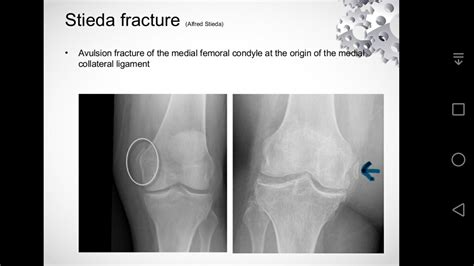

What does stieda's fracture mean? Stieda disease fracture — stie·da disease, fracture (shteґdah) alfred stieda, german surgeon, 1869â€1945 see pellegrini disease, under disease, and see under fracture … medical dictionary. Radiographs were ordered, and a fracture of a normal variant, the stieda process, was identified. Bony avulsion injury of the medial collateral ligament at the medial femoral condyle. Click on the first link on a line below to go directly to a page where stieda's fracture is defined. In some cases, the only symptom of a small fracture is a the recovery and healing time for tibial fractures differs and depends on the type and severity of the. It is calcium deposition in the area where the mcl attaches to the femur and is generally indicative of a medial collateral ligament injury. Related online courses on physioplus. What does stieda's fracture mean? Looking for online definition of stieda's fracture in the medical dictionary? It should not be confused with a stieda process fracture o. This eponym refers to avulsion of the medial femoral condyle at the origin of the medial collateral ligament. 1877) and the german surgeon a. Also visible is a fracture of the patella. It is named for the italian surgeon a. Qui ressemble à un manifeste cliniquement par. We found 5 dictionaries with english definitions that include the word stieda's fracture: